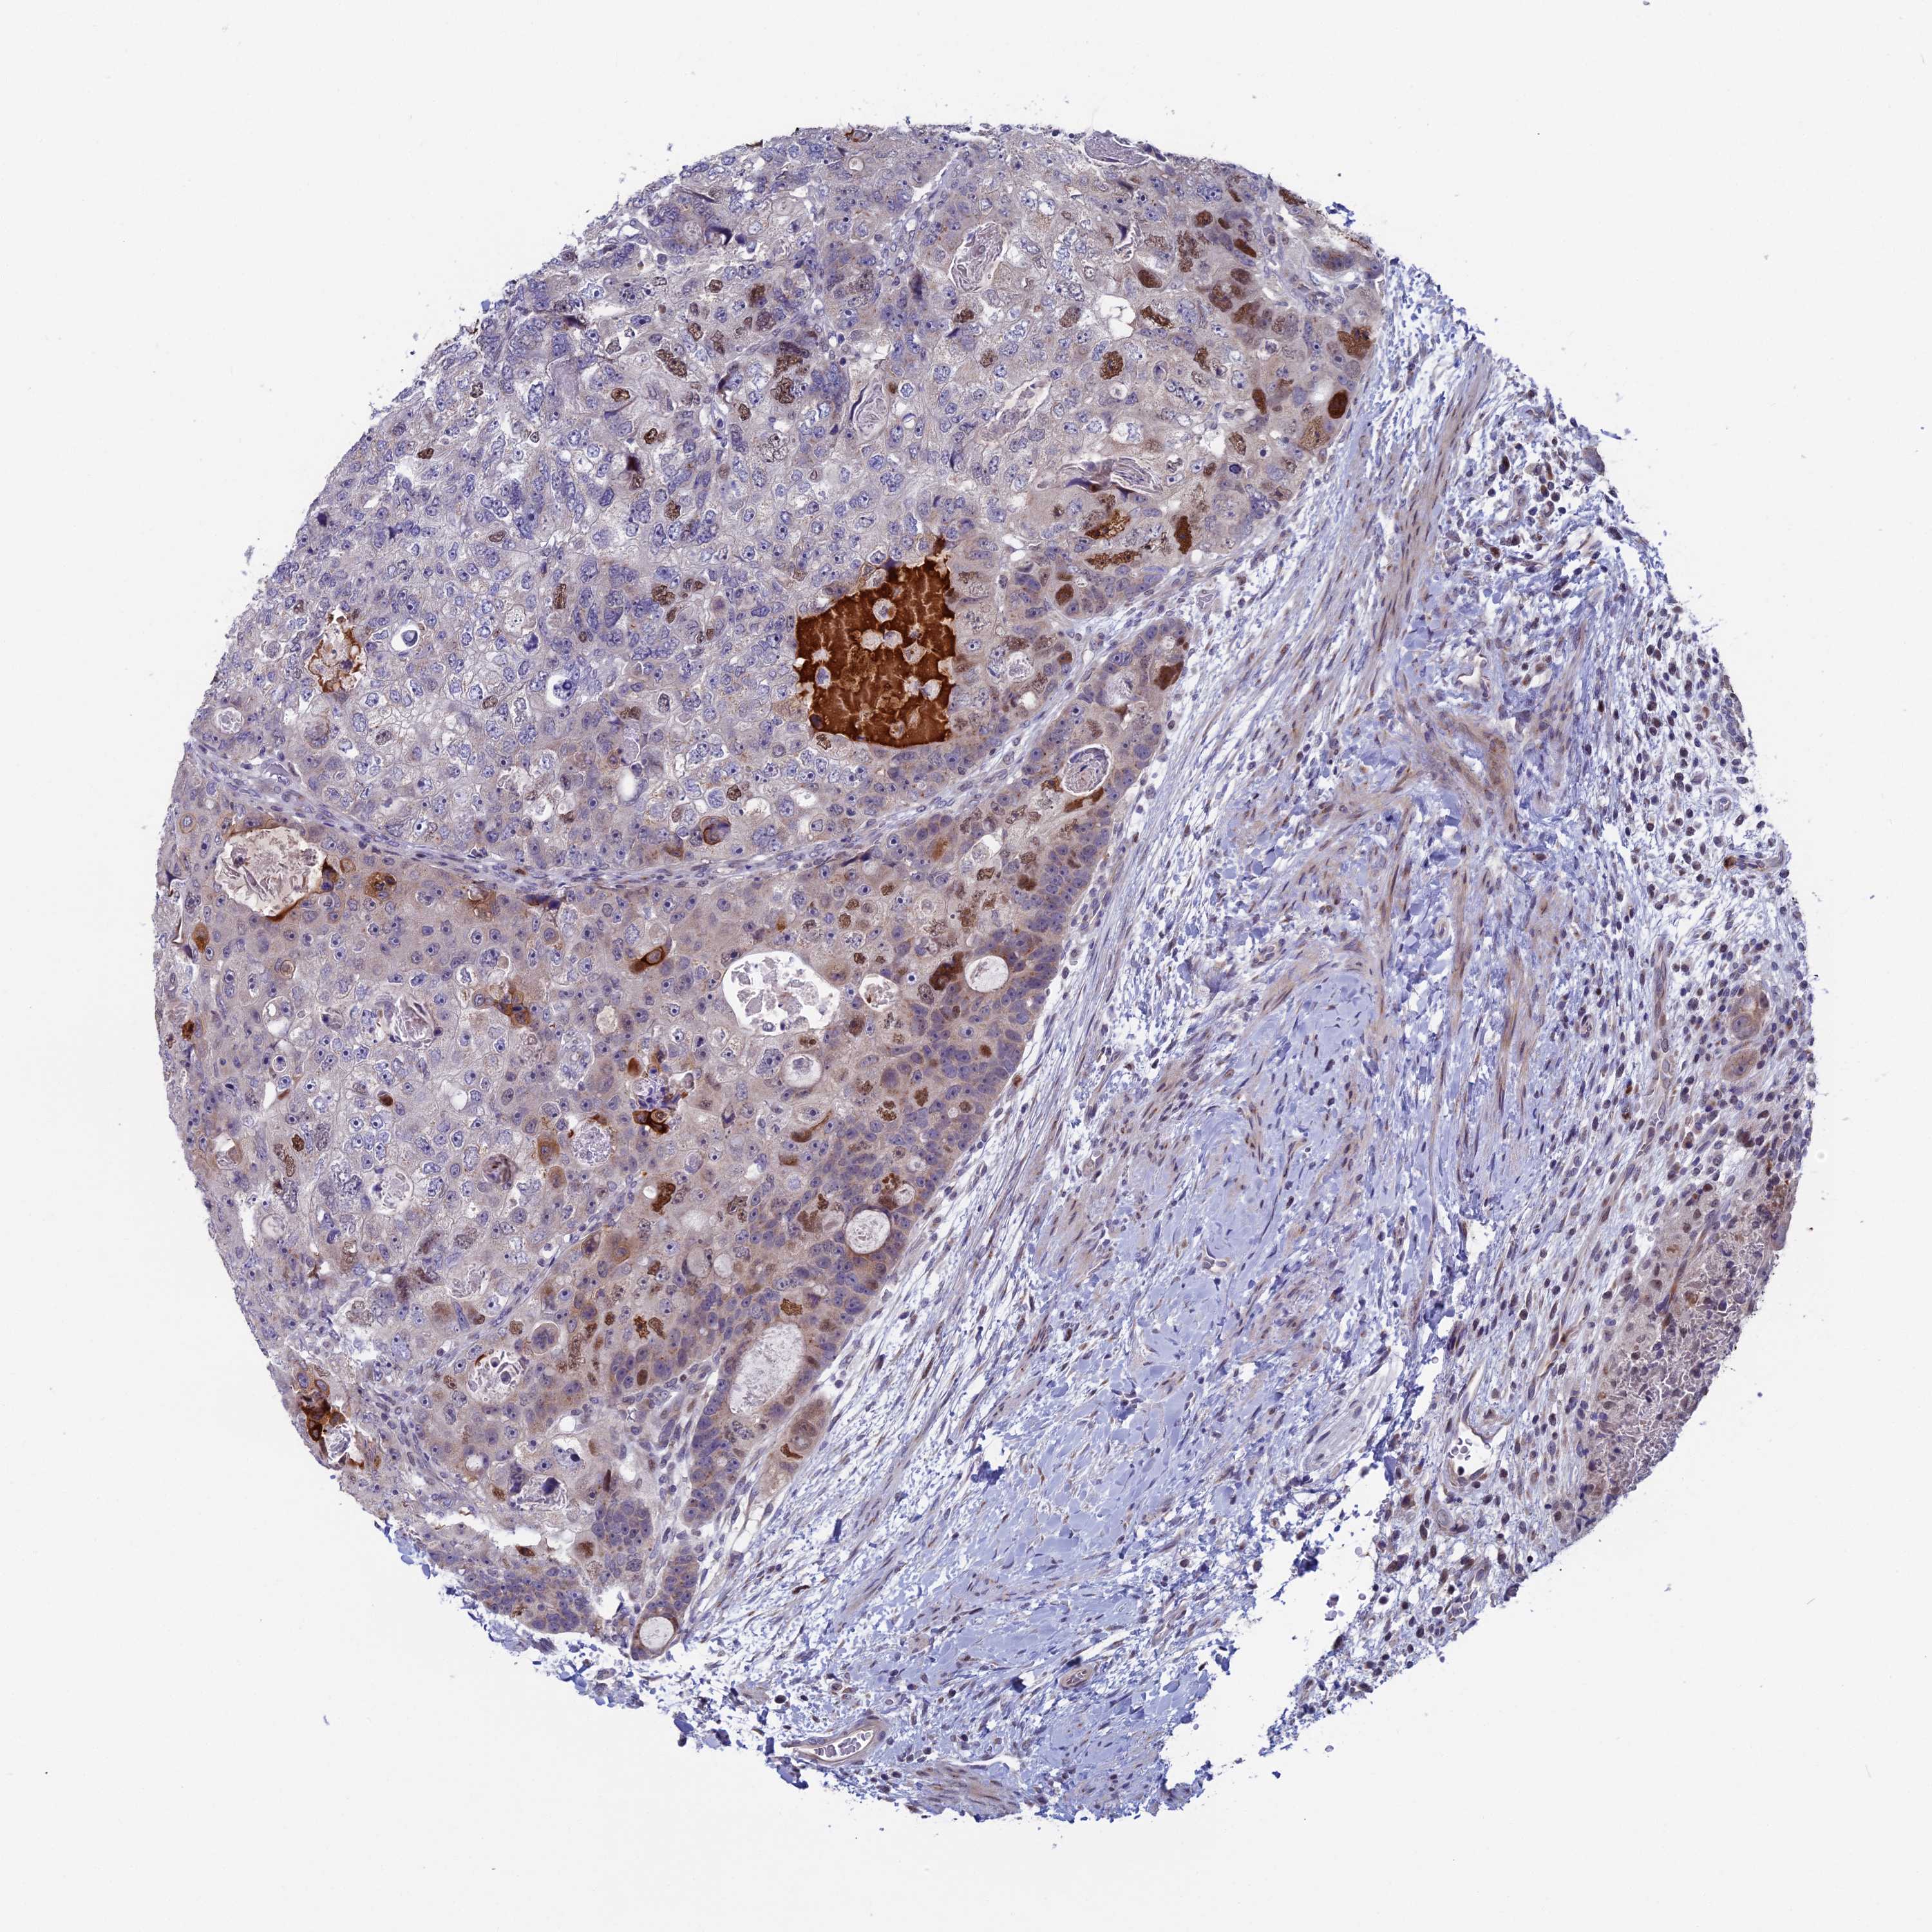

CANCER COLORECTAL CANCER Show tissue menu

Colorectal cancer

Human cancer

Colon adenocarcinoma